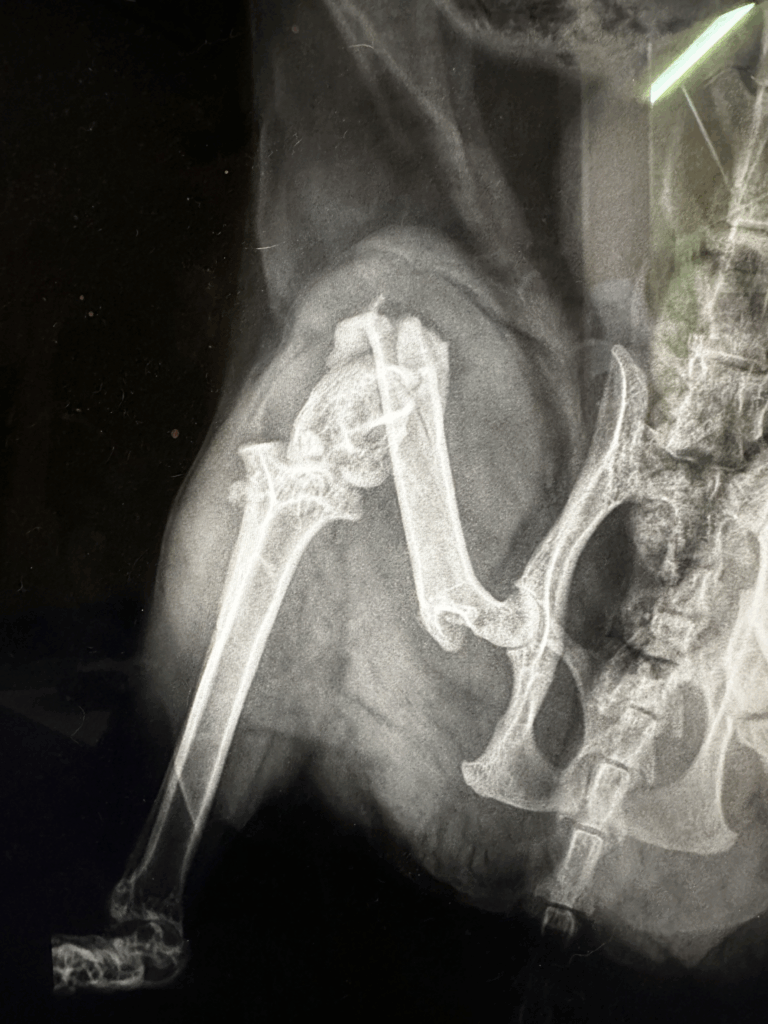

レントゲンで分かる骨折の現実

診察では触診に加え、必ずレントゲン検査を行います。大腿骨骨折にはさまざまなタイプがあり、

- 斜めに割れる「斜骨折」

- 粉々になる「粉砕骨折」

- 関節にまで及ぶ「関節内骨折」

といった形態が存在します。

特に猫の大腿骨骨折は プレートやピンなどの整形外科用のインプラントを使った手術 が必須となることが多く、ただ包帯やギプスで固定するだけではまず治りません。